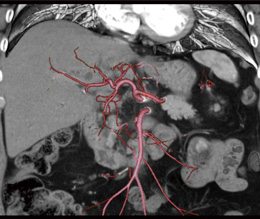

3.VR

VR(Volume Rendering)は,形状診断には欠かせない画像である。近年はカテーテルによる血管撮影の代替となりうる画像が提供可能である。脈管の走行を把握するため,観察したい血管のみの抽出がAdd Vessel機能により簡便に行える。また,肝動脈と門脈を重ね合わせたり,MPR像に重ね合わせたりと簡便に加工が可能である(図7,8)。 |

図8 肝動脈とMPRの重ね合わせ画像 |